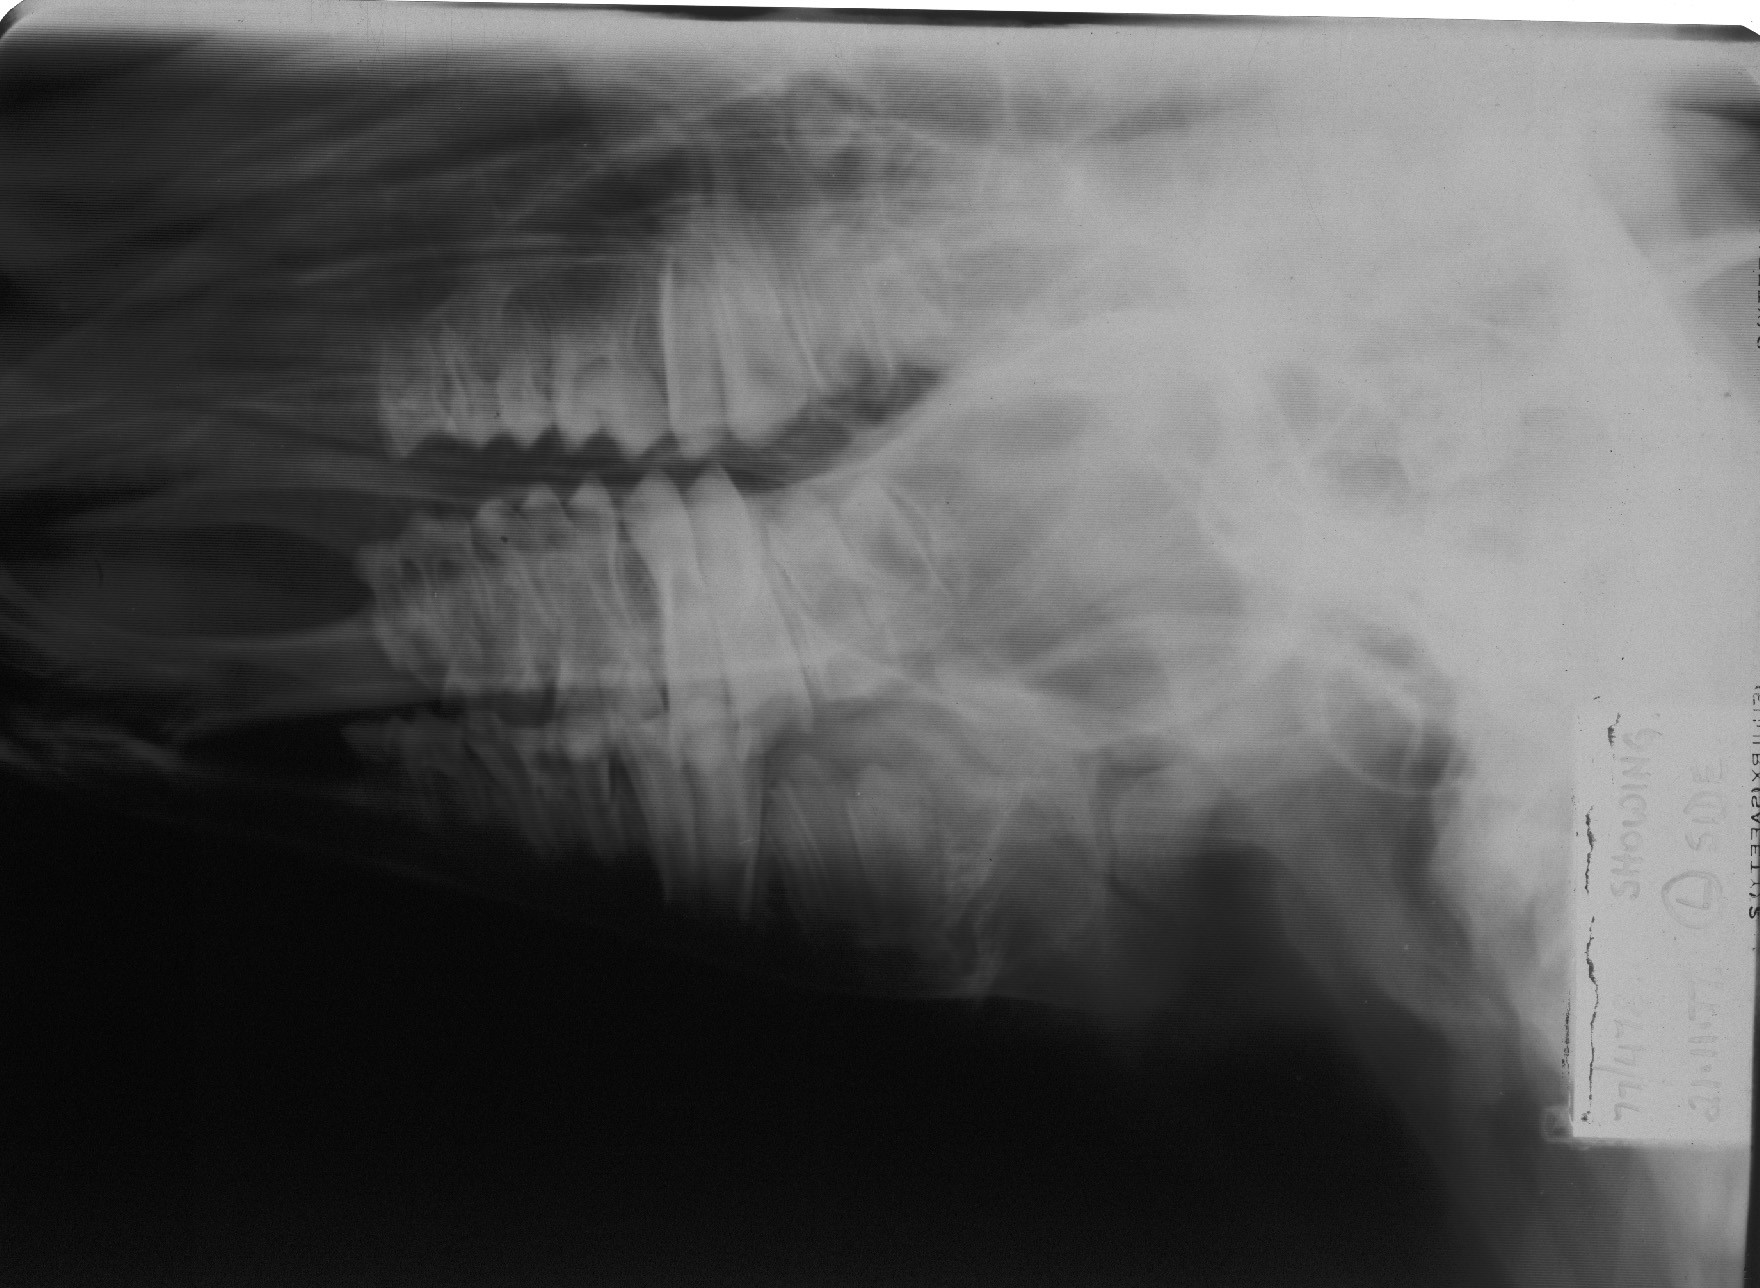

Veterinary attention is essential to establish a definitive diagnosis. Mal-alignment of the dental arcade can usually be palpated at the fracture site. The displacement at the fracture site is often slight and best appreciated by running a finger along the lingual aspect of the premolar and molar teeth. The fracture site can be demonstrated radiographically but such examination is not always undertaken in practice.

Fig 10 The fracture site can be demonstrated radiographically